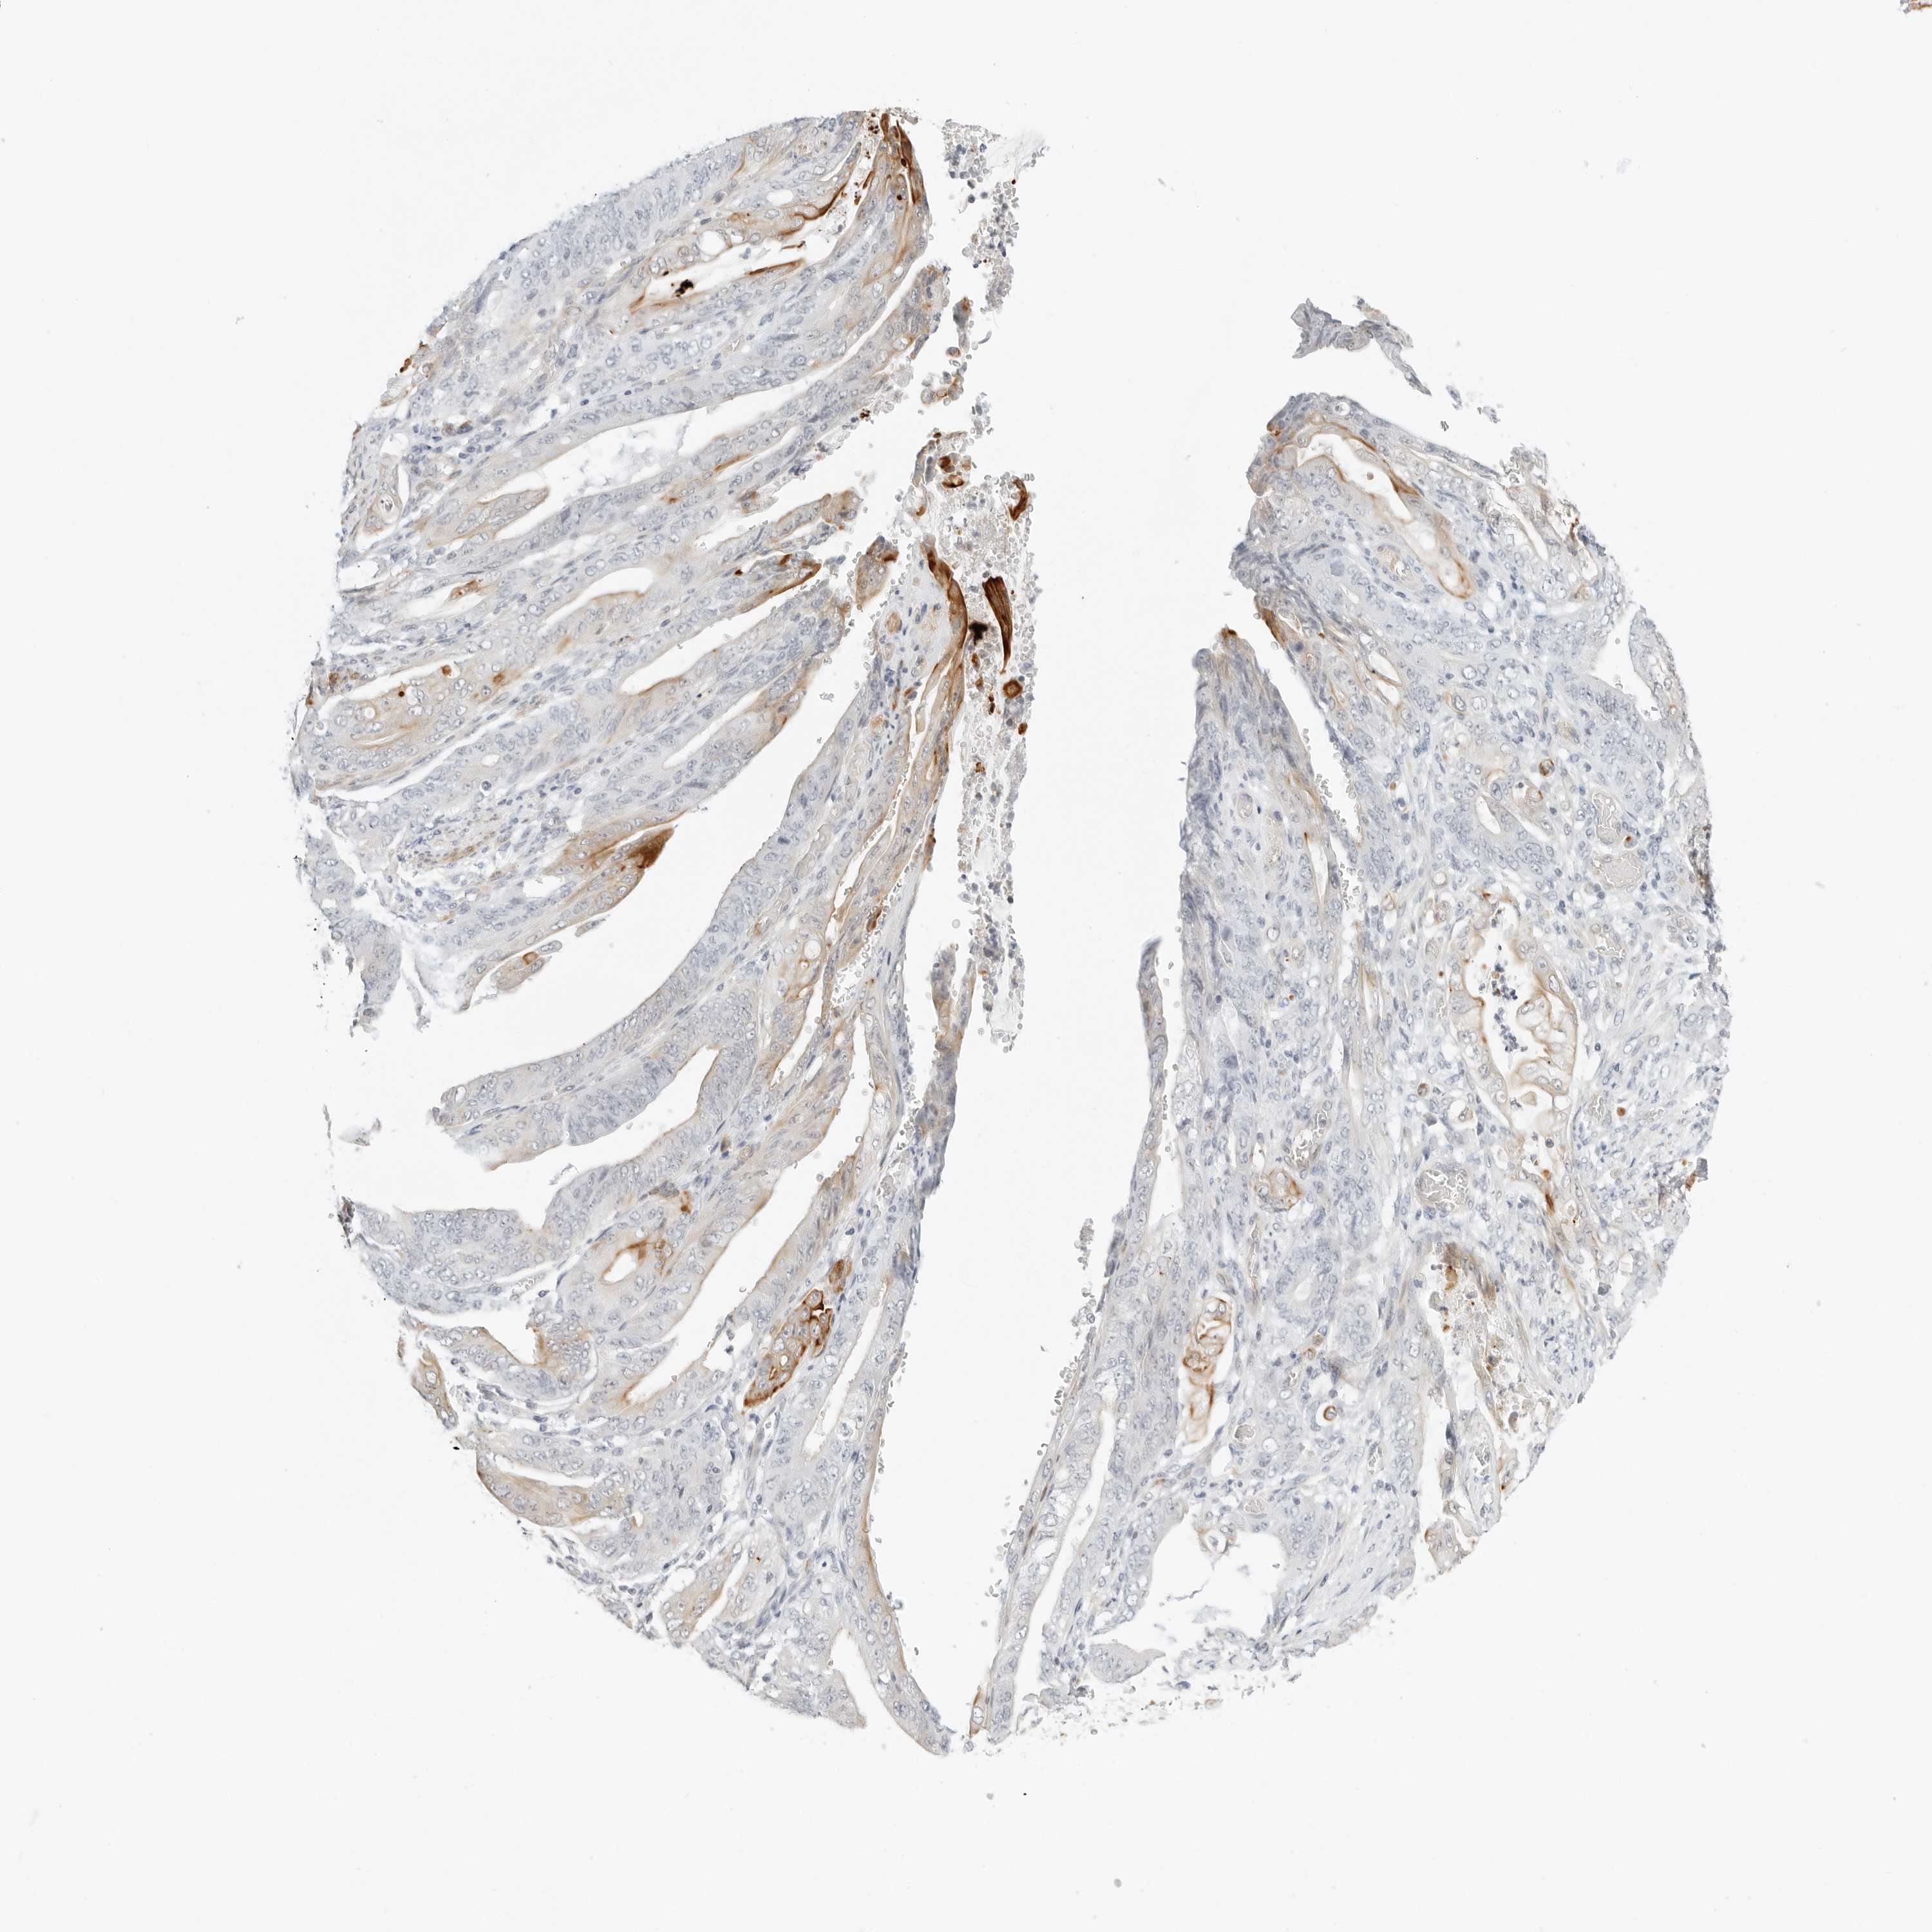

STOMACH CANCER - Protein expressioni

A mouse-over function shows sample information and annotation data. Click on an image to view it in a full screen mode. Samples can be filtered based on level of antibody staining by selecting one or several of the following categories: high, medium, low and not detected. The assay and annotation is described here.

Note that samples used for immunohistochemistry by the Human Protein Atlas do not correspond to samples in the TCGA dataset.

Antibody stainingi

Antibody staining in the annotated cell types in the current human tissue is reported as not detected, low, medium, or high, based on conventional immunohistochemistry profiling in selected tissues. This score is based on the combination of the staining intensity and fraction of stained cells.

Each image is clickable and will lead to virtual microscopy that enables deeper exploration of all samples and also displays staining intensity scores, fraction scores and subcellular localization as well as patient and tissue information for each sample.

Antibody HPA028602

Antibody HPA028686

Staining

High

Medium

Low

Not detected

Intensity

Strong

Moderate

Weak

Negative

Quantity

>75%

75%-25%

<25%

None

Location

Nuclear

Cytoplasmic/membranous

Cytoplasmic/membranous,nuclear

Adenocarcinoma, NOS